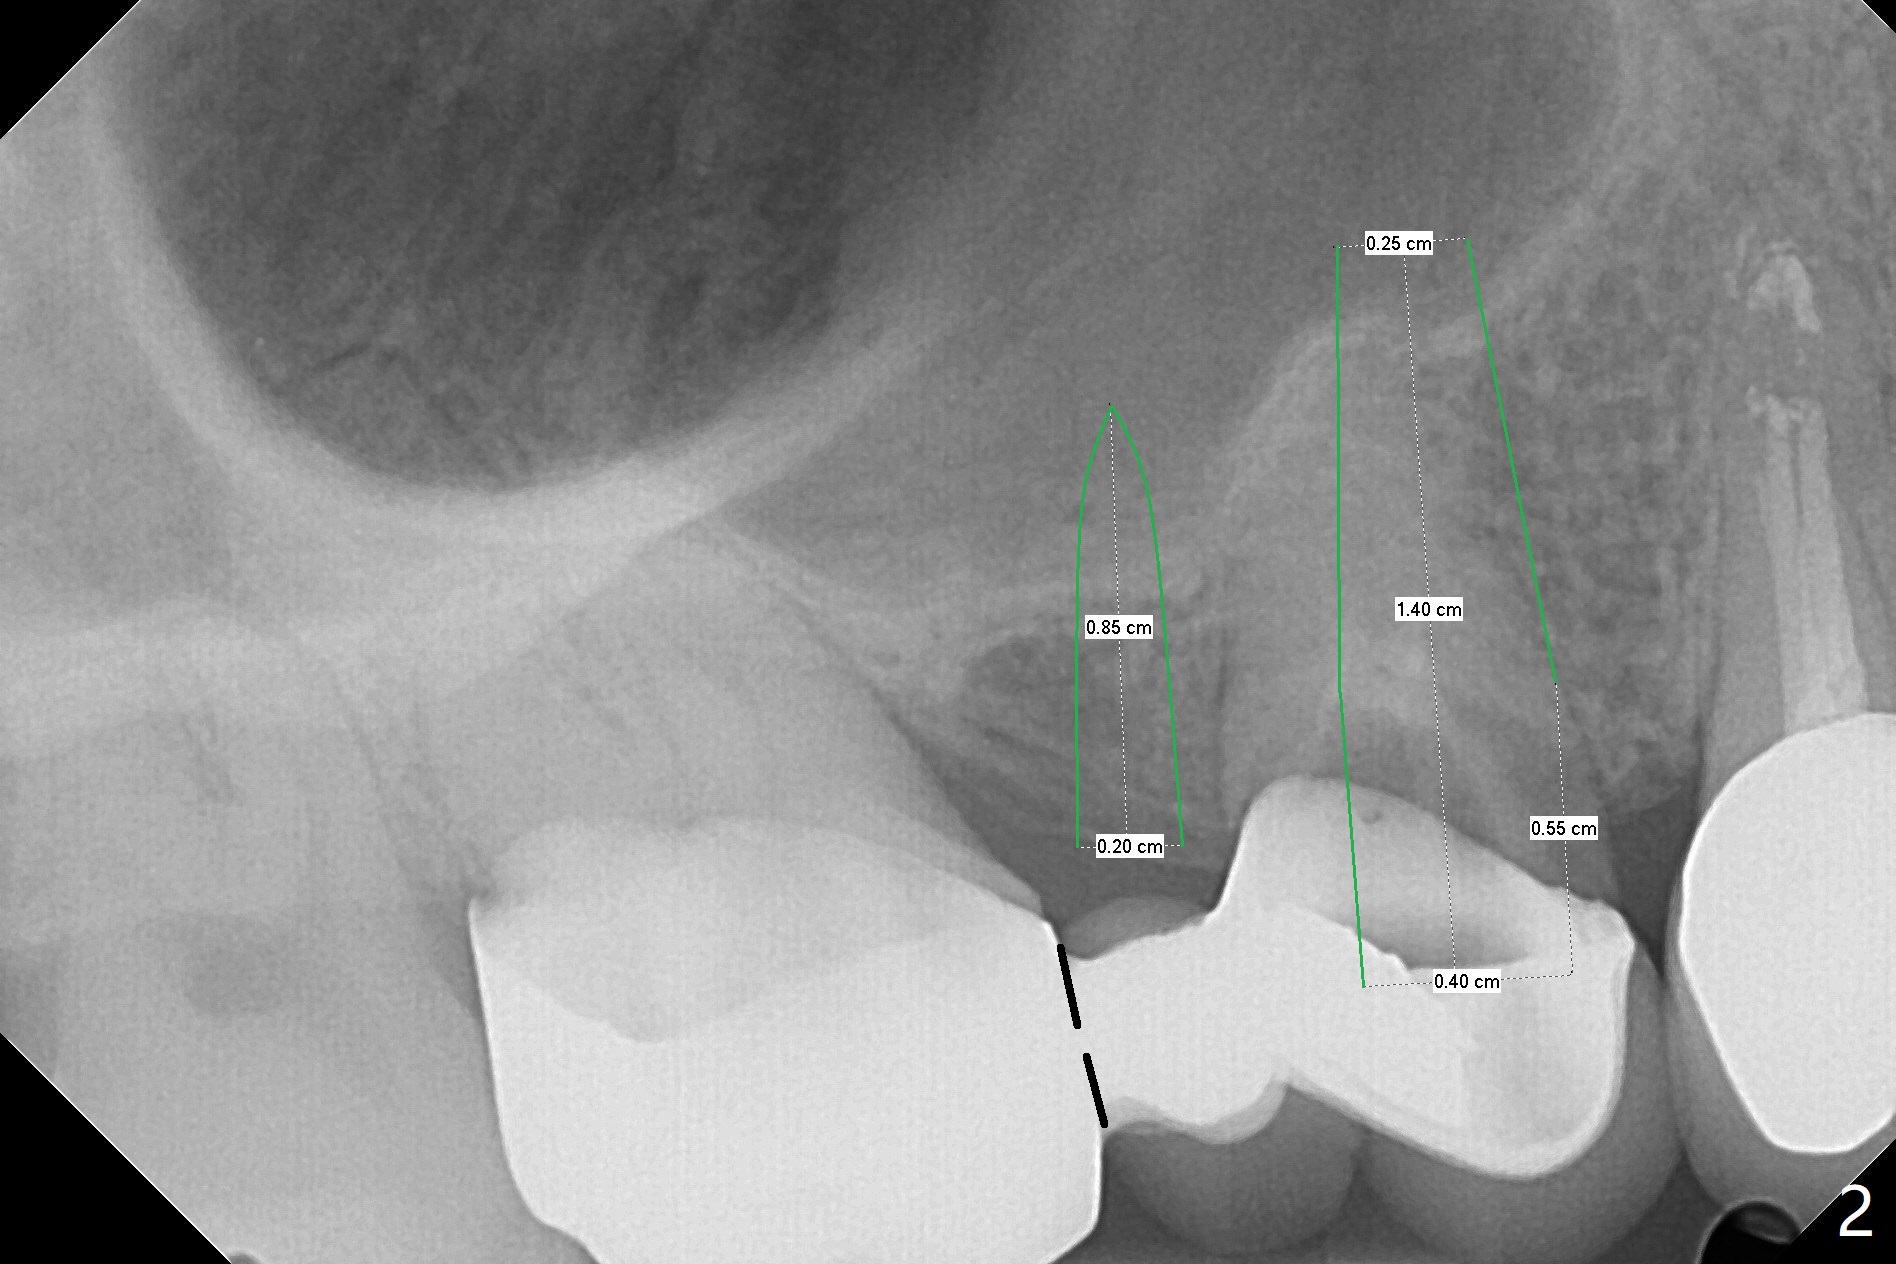

A 56-year-old man complains of food impaction under UR FPD (fixed partial denture, bridge). Floss goes through between #4 abutment and retainer (Fig.1 red arrow and *). After sectioning the FPD as indicated by black dashed line in Fig.2,3, try to initiate osteotomy at #3 with 1.2 and 1.5 mm drills for 5 mm (bone height) and 1.0 and 1.5 mm Tatum micro-osteotomes for sinus lift and place a 2x8.5 mm IS mini-implant. If it is feasible, place a 4x14 mm tissue-level implant slightly mesial at #4 (Fig.5). If not, place a larger one (5.0 mm) slightly distal for a cantilever FPD (Fig.4).